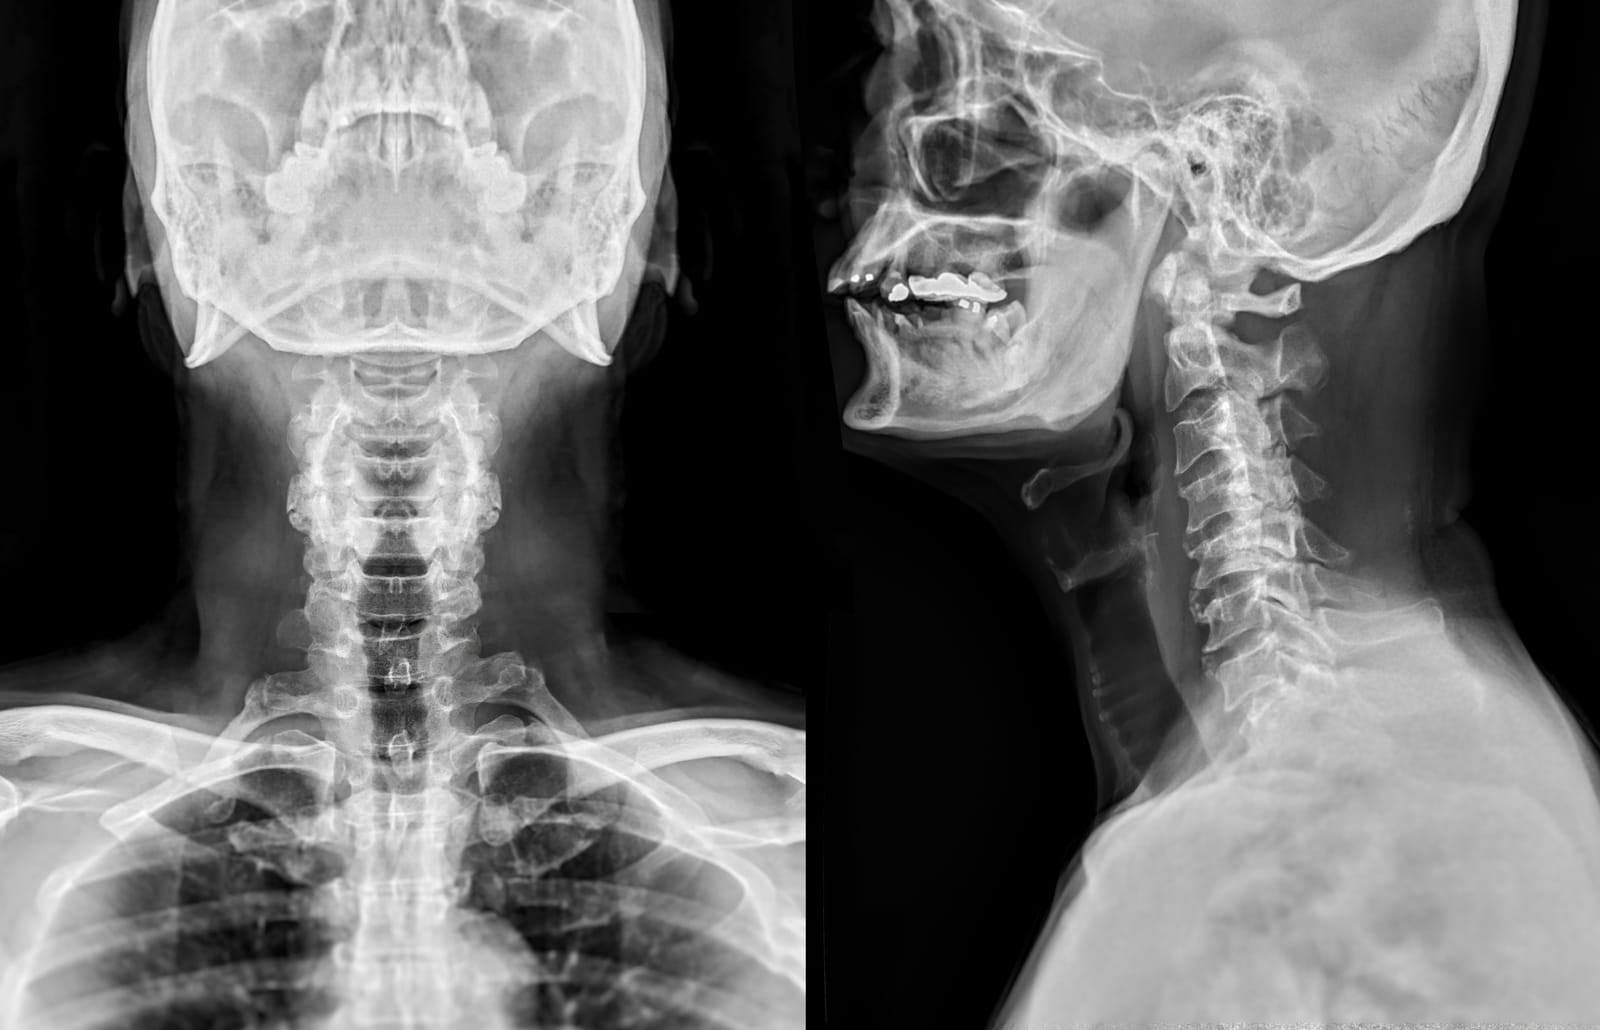

We are dedicated to providing superior diagnostic services through cutting-edge X-Ray technology, guaranteeing precision and accuracy in your medical assessments. Enjoy the advantage of receiving prompt and efficient results, enabling healthcare providers to swiftly evaluate your condition and commence suitable treatment plans. Be confident that our X-Ray procedures prioritize your safety by minimizing radiation exposure while upholding diagnostic effectiveness.